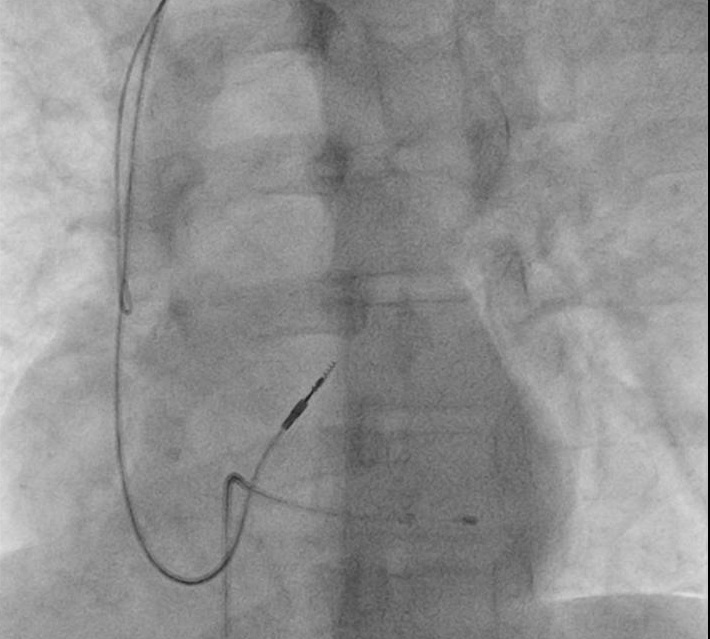

RVOT pacing

• Active fixation lead

• Stylet shaping

Mond curve

mond_curve.jpg

rvot_before_screw.jpg

rvot_lead.jpg